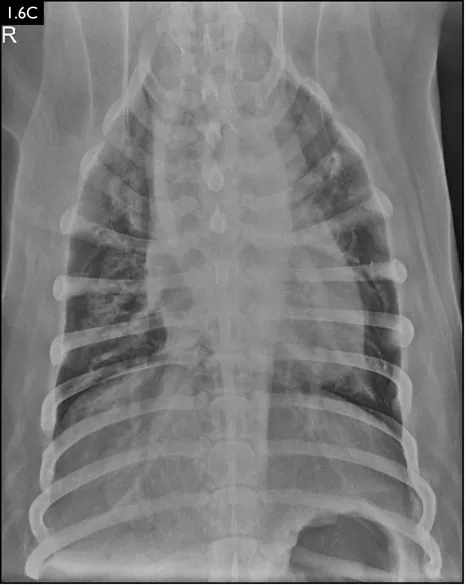

Clinical signs can be strongly suggestive of bacterial pneumonia, but radiographs are important for confirmation, to characterize the disease (and potential etiology) and to provide a baseline for monitoring response to treatment (Figs. 1.4–1.6). A lag between clinical signs and radiographic changes can occur, and initial radiographs may be normal or appear discordant with clinical severity.

Fig. 1.4A–D Lateral and ventrodorsal radiographs of a dog with doxycycline-responsive pneumonia of unknown etiology before treatment ( A, B) and six days later ( C, D). Note the severe multilobar alveolar pattern that was present initially, most prominently in the left cranial lung lobe. (Courtesy of Atlantic Veterinary College)

Fig. 1.6A–D Radiographs of a dog with suspected aspiration pneumonia. A diffuse alveolar pulm...